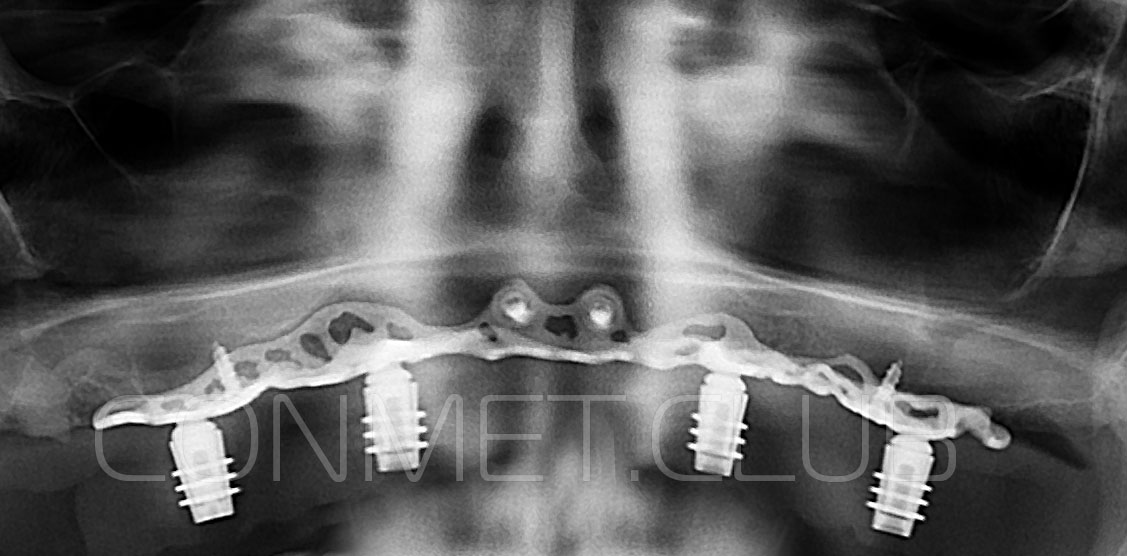

1. Пациенту было произведено МСКТ исследование нижней челюсти, с последующим созданием STL модели. В зуботехнической лаборатории был изготовлен восковой шаблон с искусственными зубами с учетом индивидуальных прикусных взаимоотношений (пока это делает зубной техник точно так же, как при изготовлении съемного пластиночного протеза).

2. После этого произвели компьютерное моделирование самого имплантата и фиксирующих элементов. Примечательно, что в абатментах, использовался отлично зарекомендовавший себя и проверенный десятилетиями интерфейс КОНМЕТ! В результате получили несколько специальных файлов, позволяющих не только сделать сам имлантат, но еще до операции изготовить и сами зубы. Данные файлы передали в изготовление на специальном 3D оборудовании.

Имплантат напечатали из особого, биосовместимого, медицинского титана на предприятии имеющим соответствующую медицинскую лицензию. Толщина имплантата составила 0,8 мм, а вес всего несколько грамм!

Сама же операция длиться 20-50 минут в зависимости от количества утраченных зубов. В процессе этой операции, после проведенной местной анестезии, делается разрез на слизистой, она приподнимается и субпериостальный имплантат укладывается на кость. После этого рана фиксируется несколькими швами и все! Через 10-14 дней мягкие ткани срастаются и надкостница надежно удерживает имплантат на месте. Нет необходимости ждать несколько месяцев, как это бывает в случае с внутрикостными винтовыми имплантатами.

Новые, искусственные зубы фиксируются к этому имплантату стандартными, трансокклюзионными винтами на 1-14 день (в данном клиническом случае на 5 сутки) и по существу являются несъемными!